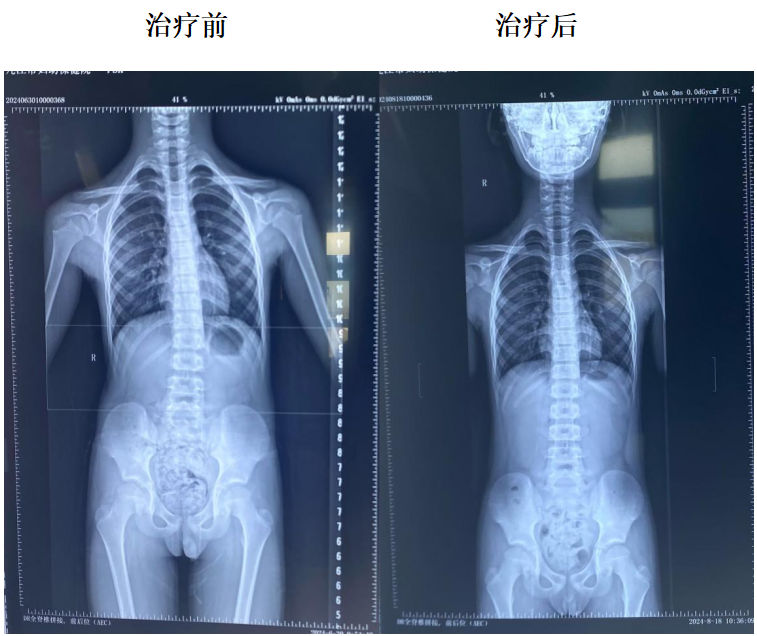

早期发现的轻度脊柱侧弯

经过积极康复干预

可以有效防止侧弯进展加重

避免手术